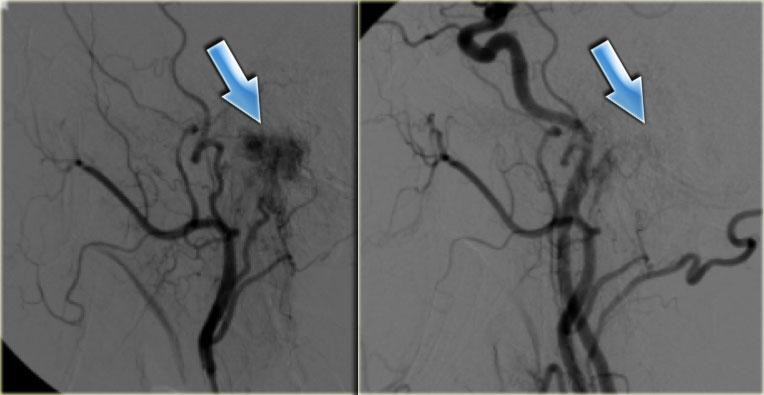

Hình bên trái là hình ảnh chụp mạch động mạch cảnh ngoài trái trước thuyên tắc và động mạch cảnh chung sau thuyên tắc (mũi tên xanh).

Chỉ còn lại một vệt ngấm thuốc mờ nhạt.